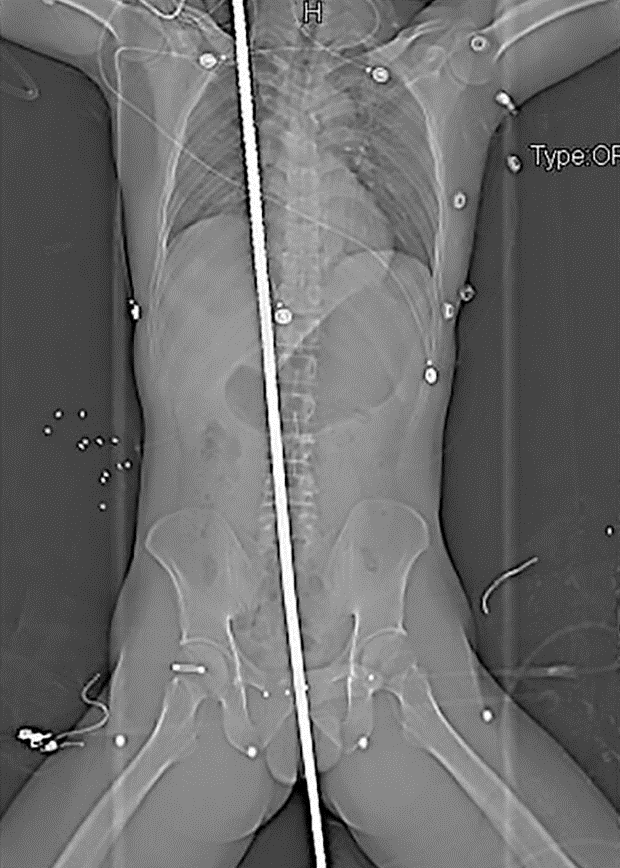

Dalam kejadian di tapak binaan di Chengdu, China itu, besi berkenaan tercucuk dari bahagian dubur mangsa hingga ke bahu kanannya.

Insiden ngeri itu mengakibatkan Yang Ming terpaksa melalui proses pembedahan selama tujuh jam bagi mengeluarkan rod besi itu.

Bagaimanapun pekerja berusia 37 tahun ini bernasib baik kerana ia tidak mencederakan organ dalamannya.

Ketua pakar bedah Hospital Universiti Sichuan, Wang Xin berkata, pesakit tidak menunjukkan sebarang tanda pendarahan pada dada atau abdomen.

"Tekanan darah dan denyutan jantungnya juga stabil," katanya yang berjaya mengeluarkan rod besi itu.

Menurut Ming, usus, pundi kencing, pankreas, paru-paru dan hatinya mengalami sedikit kecederaan, tetapi tiada organ dalaman berdepan situasi serius.